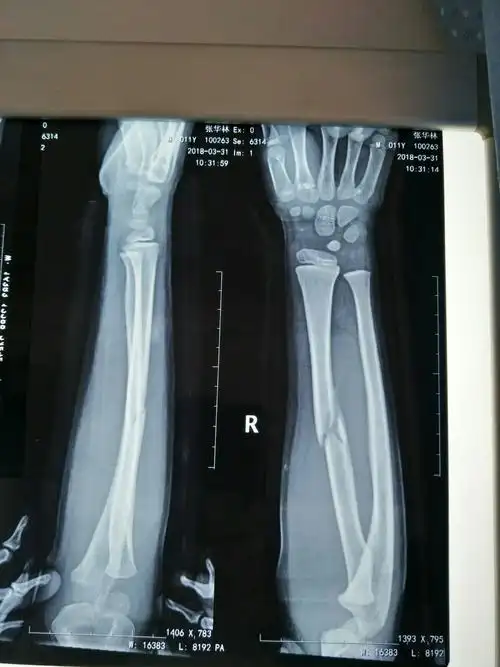

请大家看看张x光片,桡骨远端骨折复位前后

x线前臂长骨骨折判断左右的方法